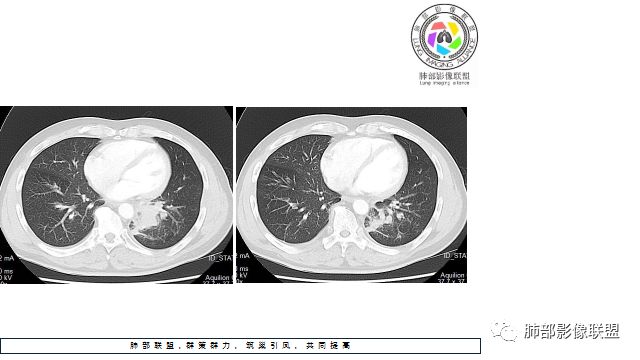

1.左下肺门区巨大肿块,支气管显示不清,轻度阻塞性炎症,没有明显肺不张,提示管腔受压狭窄可能性大于堵塞,这较少见于鳞癌。

3.病灶内密度均匀,轻到中度均匀强化,大病灶未见明显液化坏死区及空洞,不符合鳞癌而符合小细胞肺癌特点。

4.病灶内有肺动脉走形,血管局部受压,未见破坏,病灶乏血供,呈血管包埋或血管造影征;侵袭性力强及破坏力弱、血管漂浮都符合SCLC,所以鳞癌的可能性也不大。

5.左肺门块影或淋巴结肿大,竭力挤兑肺门血管结构,呈冰冻肺门;有时候SCLC可以单独呈现冰冻肺门,而没有没有冰冻纵隔。